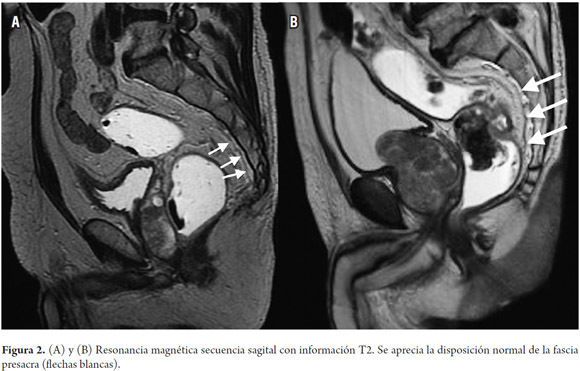

RESONANCIA NUCLEAR MAGNETICA

Mejpr estudio para ver detallada la anatomia. Se pide en paciente que no puedes ser contrastados o no se pueden irradiar. Contraindicacion en pacientes que usan implantes ferromagneticos. T1 es bueno para ver anatomia: blanco: grasa, hemorragia, sustancia blanca. Gris; sustancia gris, higado, bazo, pancreas, riñon, musuclo, lesines con agua, Negro: orina, quistes, tendones, vasos, aire T2 es bueno para ver patologia. Blanco: orina, quistes, tumores, riñon, bazo, agua libre, LCR. Gris; sustancia gris, grasa. Negro: pancreas, higado, musculo, hueso cortical, tendones, aire, vasos. Como los cambiospatologicos son inflamatorios o tumorales, cambios de edema(aumento de agua). En T2 el agua es blanca por lo que las lesiones se ven hiperintensas en T2.

La uro resonacnia no sirve para ver piedras comparado con el uro TC Cancer de vejiga: leccion para su etapificacion ya que permite ver la pared vesical. Cancer de prostata; Score PIRADS, compromiso pared prostata, de vesiculas seminales.